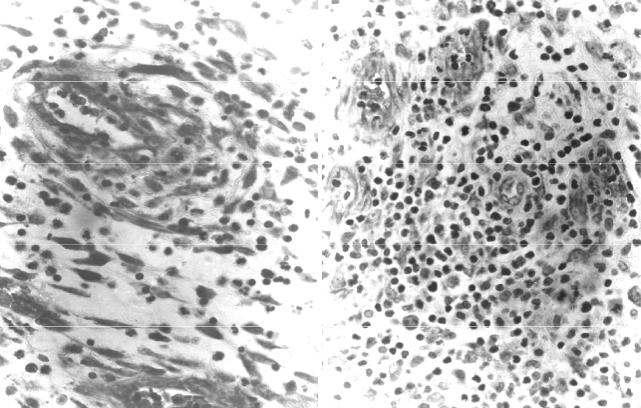

Рис. 18. Репаративная регенерация в ранах (окраска гематоксилином и эо- зином): а организация некроза в ране после первичной хирургической обра- ботки с ее заживлением первичным натяжением, 7-е сутки (× 100); б началь- ные признаки образования грануляционной ткани в жировой клетчатке под де- маркационным лейкоцитарным валом при развитии нагноения раны, 7-е сутки (× 100); в сформированная грануляционная ткань отграничивает зону гной- ного расплавления некротизированных тканей при заживлении раны вторич- ным натяжением, 25-е сутки (× 75)

а

б

Рис. 20. Формирование грануляционной ткани в огнестрельной ране (ок- раска азуром II и эозином, × 200): а пролиферация перицитов с образовани- ем, при участии лимфоцитов и макрофагов, периваскулярной муфты, 7-е сутки после ранения; б полиморфный клеточный состав грануляционной ткани, явления бласттрансформации лимфоцитов в их скоплениях вокруг тонкостен- ных сосудов с набухшим эндотелием, 10-е сутки после ранения